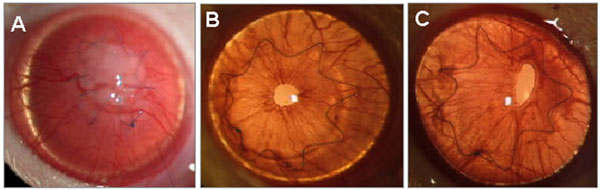

Figure 3.

Representative cases of each treatment group on slit-lamp examination at the thirteenth postoperative day showing a rejected corneal graft (A) with a maximal clinical score and two clear grafts from the systemic CsA (B) and Debio088 (C) treated groups.